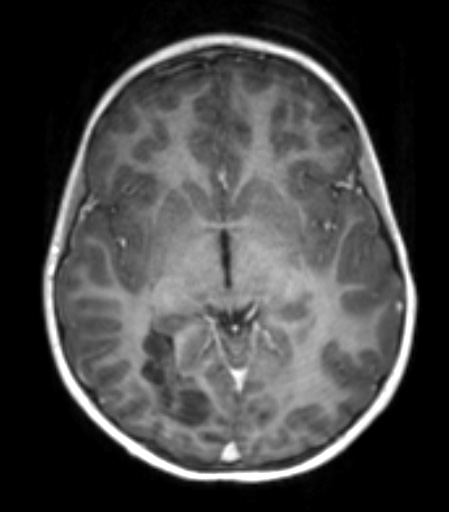

Case 29 History ---- The patient is a 6-year-old girl with refractory epilepsy and a non-enhancing, cortically-based mass in the right occipital lobe. Operative Procedure: IMRI craniotomy for tumor excision. ---- 29A1 This T1-weighted contrast-administered MRI scan shows a hypointense occipital multi-nodular lesion.